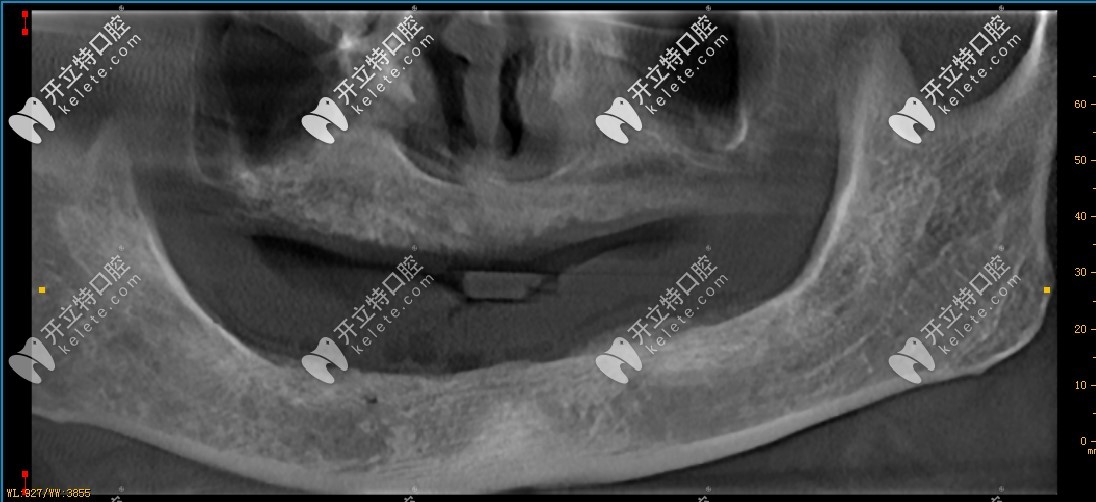

診斷情況:牙槽骨萎縮,需要采用德國(guó)生長(zhǎng)因子種植技術(shù),采取ALL-on-6即刻種植,上下各6顆植體,再制作連橋冠,共計(jì)24顆牙冠。

來(lái)看效果:從牙片來(lái)看,植體已經(jīng)植入牙槽骨內(nèi),接下來(lái)只需等待三個(gè)月的恢復(fù)期即可,不管是植入的深度或角度,都非常好!